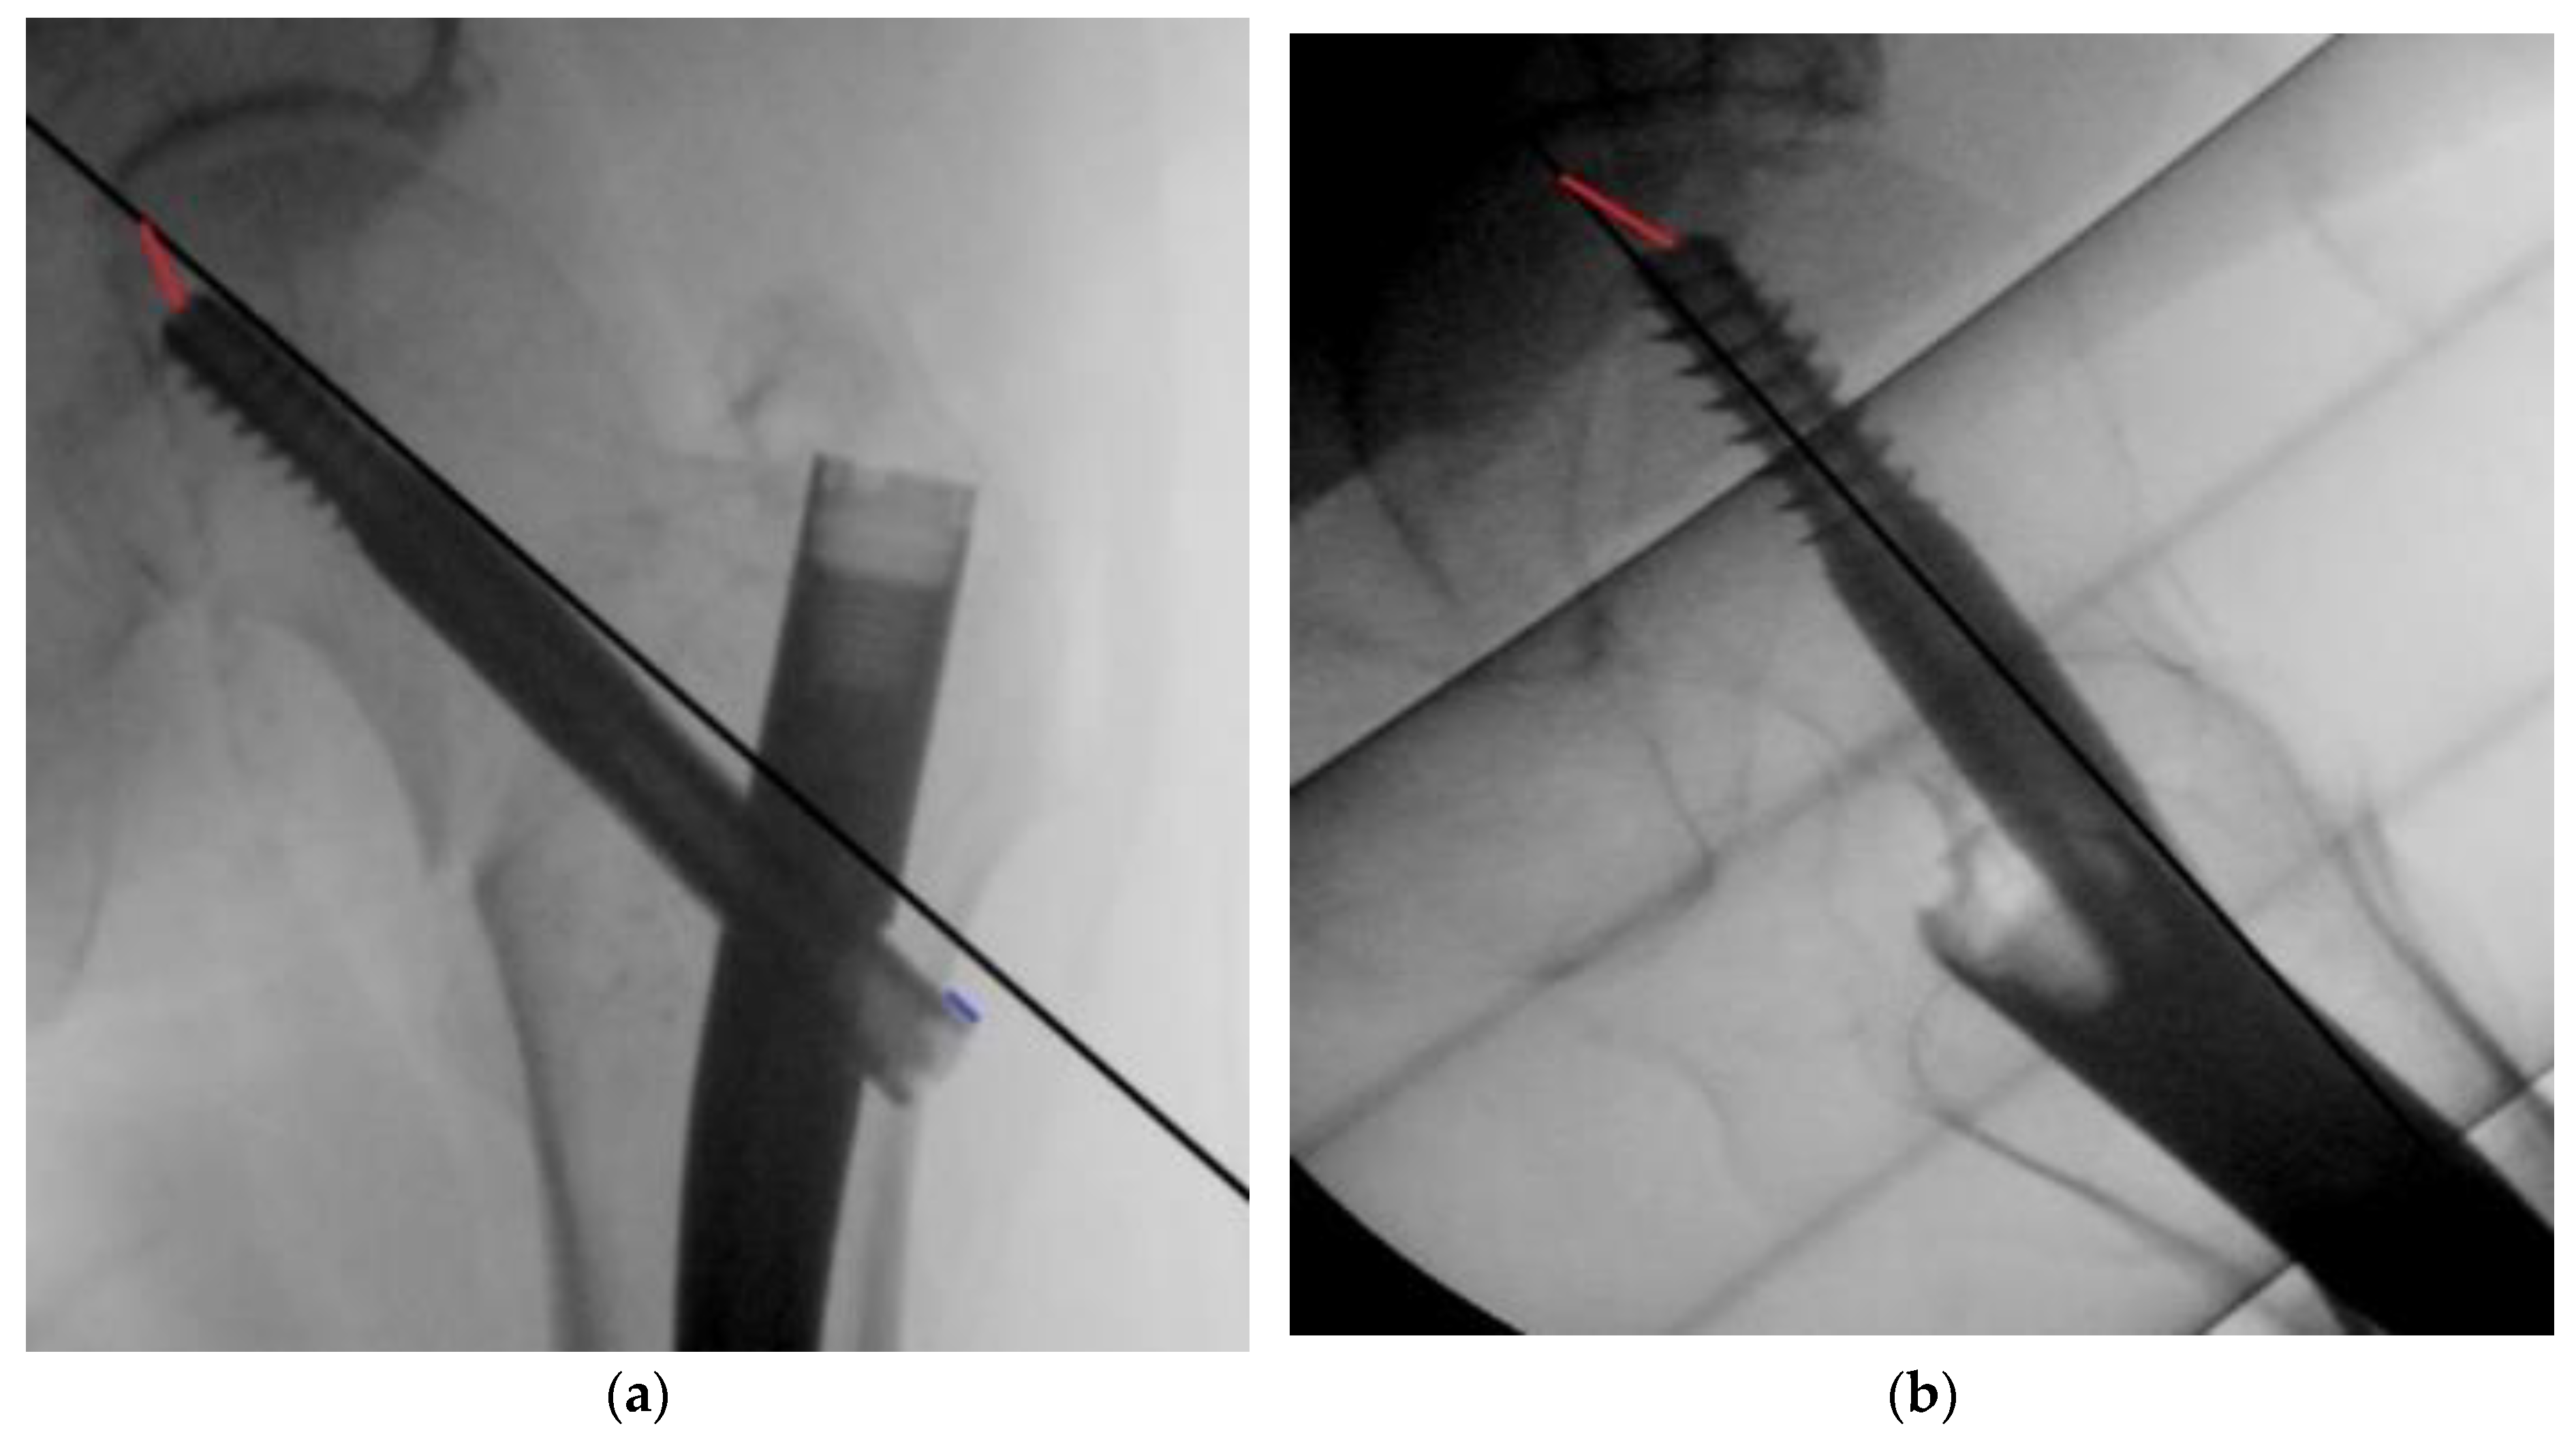

The primary outcome was the number of outliers, defined as a TAD > 20 mm and a TAD > 25 mm. The secondary outcomes were the lateral screw protrusion (Figure 1), median TAD, duration of surgery, and fluoroscopy time.

The TAD was measured based on perioperative fluoroscopy images using the method described by Baumgaertner et al. [3], where the distance from the screw tip to the apex of the femoral head in both the anteroposterior and lateral planes is used to generate a single numerical value for the TAD, calibrated by measuring the known diameter of the lag screw. The lateral screw protrusion was calculated in a similar manner (Figure 1).

Figure 1. (a) Measuring the distance from lag screw tip to apex in the antero-posterior plane (red line) and the lag screw lateral protrusion (blue line). (b) Measuring the distance from lag screw tip to apex in the lateral plane (red line).